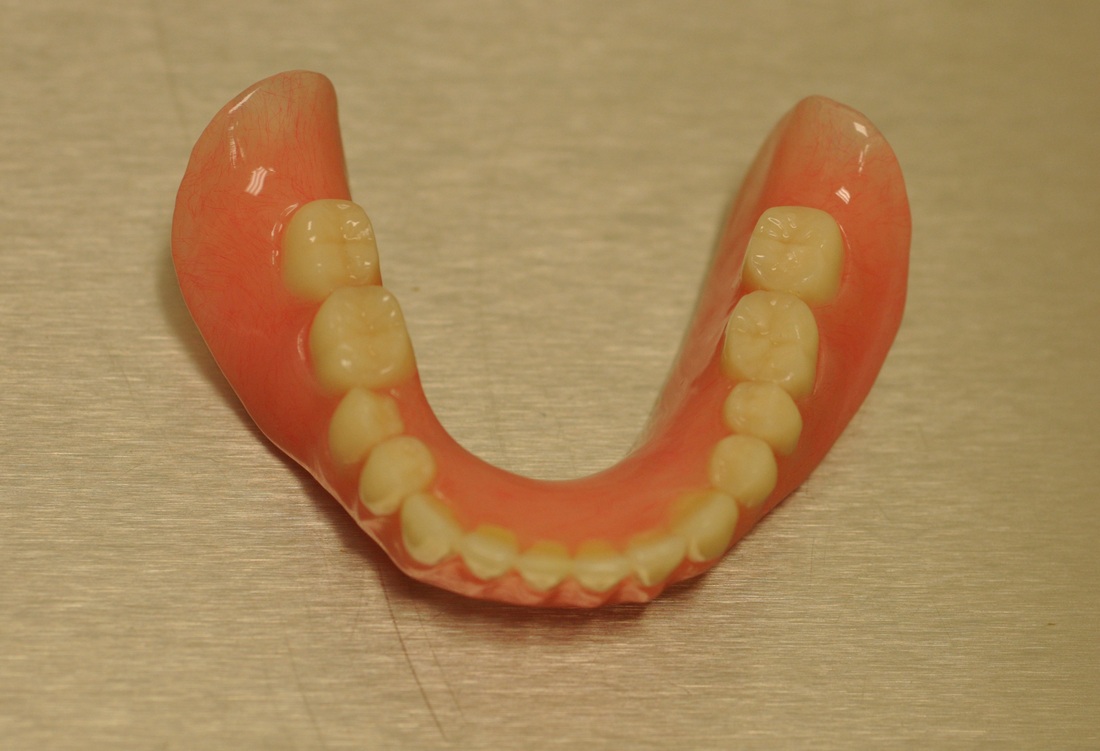

Lower Denture Stabilization

DENTURE STABILIZATION

This patient’s existing old partial denture became loose after one of her teeth had broken. After thorough dental examination Dr. Andrews recommended to extract remaining lower teeth and immediately place two regular size dental implants in order to stabilize a new full lower denture.

During only one surgery three lower teeth were removed, two dental implants were placed. Three months later two snap-on attachments were placed on the integrated implants.

Her speech and chewing ability has instantly significantly improved. The satisfied patient regained quality of life she desired and expressed desire to replace the old upper denture with a new one as well.